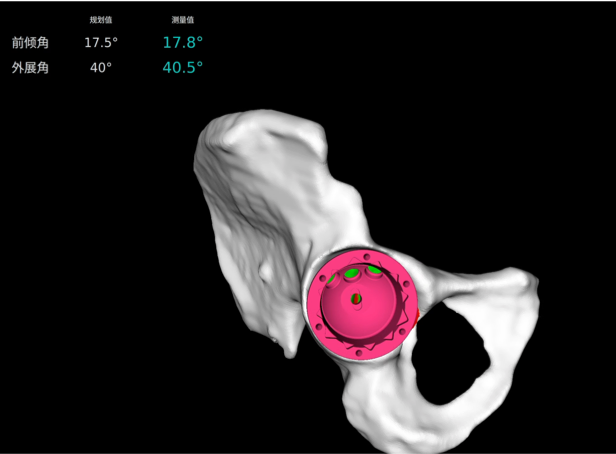

· 個性化規(guī)劃假體尺寸及安裝角度,預(yù)估安裝效果。

· 融合 CT 和 3D 模型,直觀顯示假體植入效果。

· 制定詳細(xì)植入計(jì)劃,術(shù)前預(yù)演

· 精準(zhǔn)高效執(zhí)行手術(shù)操作,實(shí)時安裝角度顯示,誤差控制在1°以內(nèi)。